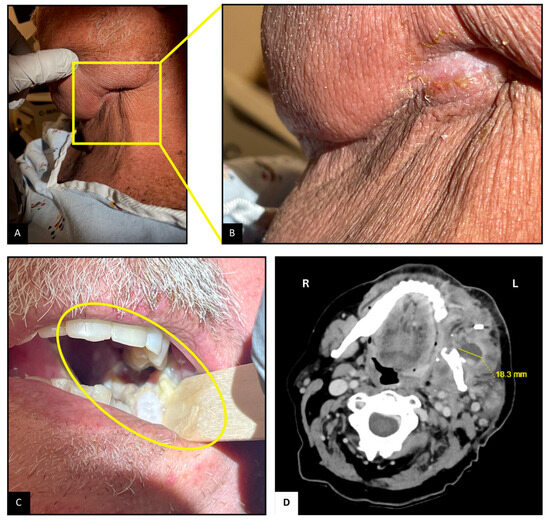

A Rare Case of Cervicofacial Nocardiosis and Associated Mandibular Osteomyelitis: Therapeutic Challenges in a Transplant Patient

Cervicofacial actinomycosis is a well-recognized infectious disease caused by Actinomyces, a Gram-positive filamentous bacterium. In contrast, Nocardia, a morphologically similar, hyphae-forming organism, is an exceedingly rare cause of cervicofacial abscesses, and even more uncommon associated osteomyelitis of mandible. We present such [...] Read more.

Cervicofacial actinomycosis is a well-recognized infectious disease caused by Actinomyces, a Gram-positive filamentous bacterium. In contrast, Nocardia, a morphologically similar, hyphae-forming organism, is an exceedingly rare cause of cervicofacial abscesses, and even more uncommon associated osteomyelitis of mandible. We present such a case involving a kidney transplant recipient who presented with opioid-induced constipation, along with left jaw pain and swelling. CT scan of the soft tissue in the neck revealed a complex cervicofacial abscess with enhancement of underlying mandible. Culture growth and RNA sequencing of USG-guided aspirate identified a Nocardia species closely related to N. beijingensis/exalbida. The patient initially received broad-spectrum antibiotics, including ceftriaxone, imipenem, and trimethoprim-sulfamethoxazole (TMP-SMX). Imipenem was later discontinued in view of new-onset unexplained encephalopathy and replaced with linezolid, which was subsequently switched to minocycline following thrombocytopenia development. Minocycline therapy was intended for a total of 12 months. TMP-SMX was avoided long-term due to avoid nephrotoxicity risk in kidney transplant patients. On six-month follow-up, the patient showed clinical and radiological improvement; minocycline was discontinued after additional six months. This case highlights the importance of considering Nocardia as a differential diagnosis in immunosuppressed patients presenting with cervicofacial symptoms, especially following orofacial surgery or trauma. Early recognition, prompt diagnosis, and appropriate antibiotic therapy with adequate bone penetration seem crucial for optimal management and may help avoid the need for surgical intervention. Full article